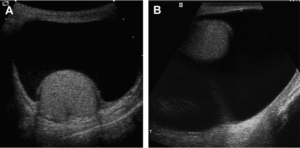

Чаще всего новообразование полостное или целостное, гладкое, мягкое, при аппаратном исследовании видны четкие контуры, гипоэхогенность говорит о заполнении жидкостью. Вместе с этим могут выявляться дистрофические или метаболические изменения.

- ультразвуковое исследование мошонки;

Для того чтобы выяснить почему в правом или в левом яичке скопилась непонятная жидкость, пациенту первым делом производят ультразвуковое обследование (УЗИ).

На этом аппарате можно качественно разглядеть картину происходящего. И разумеется, спутать кисту с водянкой невозможно. При УЗИ врач может увидеть, в каком состоянии находится половая система мужчины и выявить подобную патологию.